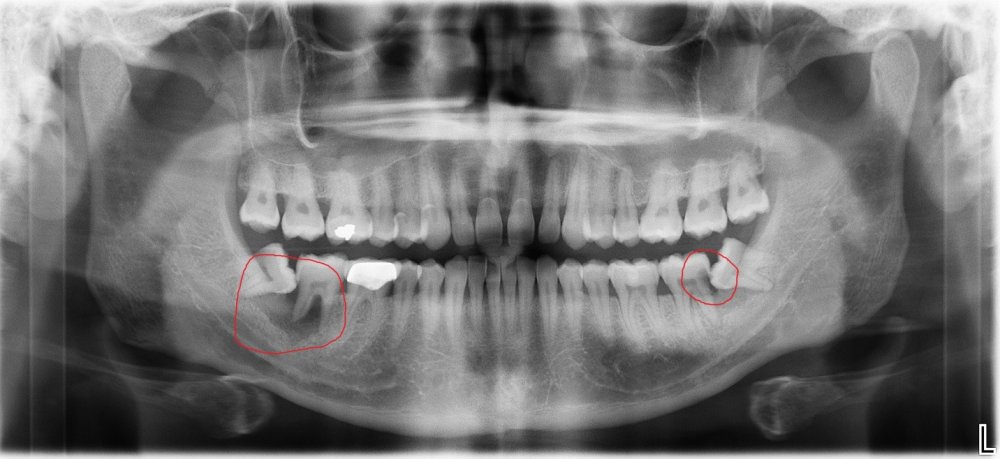

Normal halda insanın diş sırasında hər çənədə iki ədəd olmaqla, ümumilikdə dörd agıl dişi mövcuddur. Ağıl dişinin çıxması bəzi şəxslərdə heç bir kliniki əlamət və ya şikayətə səbəb olmasa da, bir çox hallarda müəyyən kliniki əlamətlərlə öyünü biruzə verir. Bu əlamətlər əsasən çənənin arxa tərəfində təzyiq, çənəni açıb baglama əsnasında agrı və məhdudlaşma kimi özünü göstərə bilir. Bu hallarda mütəxəssis konsultasiyasının önəmi olduqca böyükdür. Belə ki müayinə zamanı cərrah-stomatoloq kliniki və radioloji dəyərləndirmə apararaq dişin dogru pozisiyada yerləşib yerləşmədiyi, dişləmə çıxma ehtimalını, agıl dişinin çənəyə görə ölçüsü və çənə darlıgı kimi durumları dəyərləndirərək tətbiq edilməli olan müalicə taktikasını müəyyən edir.

- Retensiyon ağıl dişinin spontan və ya ortodontik olaraq dişləmə çıxma ehtimalı mövcud deyilsə

- Ağıl dişi qonşu dişdə karies, sorulma, parodontal problemlər və s. yaradırsa

- Ağıl dişi qonşu dişin çıxmasına məhdudiyyət yaradırsa və diş sırasında deformasiyalara səbəb olursa